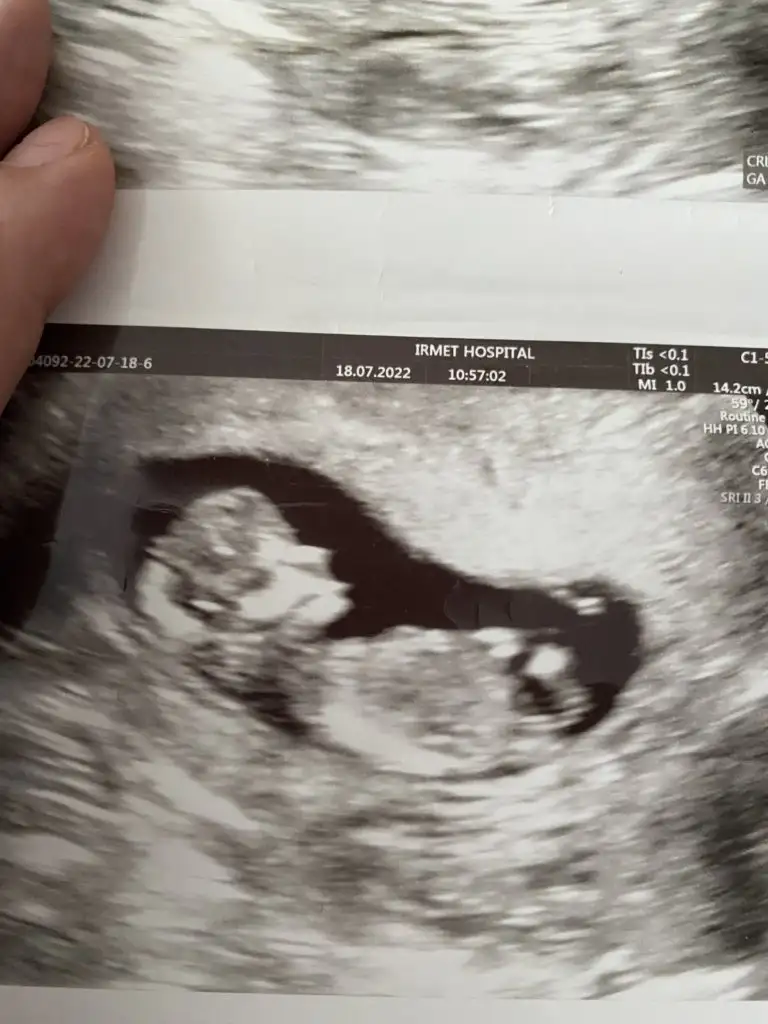

dr soylemeden siz gorun genital nub teorisi ( bebegin cinsiyeti)

Doktor birtürlü emin olamıyor ya nasıl iş anlamadım erkek testisi göremiom dedi kıza benzio ama emin değilim dio kızdır herlde ya

17 haftalık olmuş daha nasıl göremedi anlamadım ilginçmiş valla. Başka bir doktora da gitseydiniz keşke bende perşembe günü gideceğim bakalım bir şey öğrenebilecek miyim